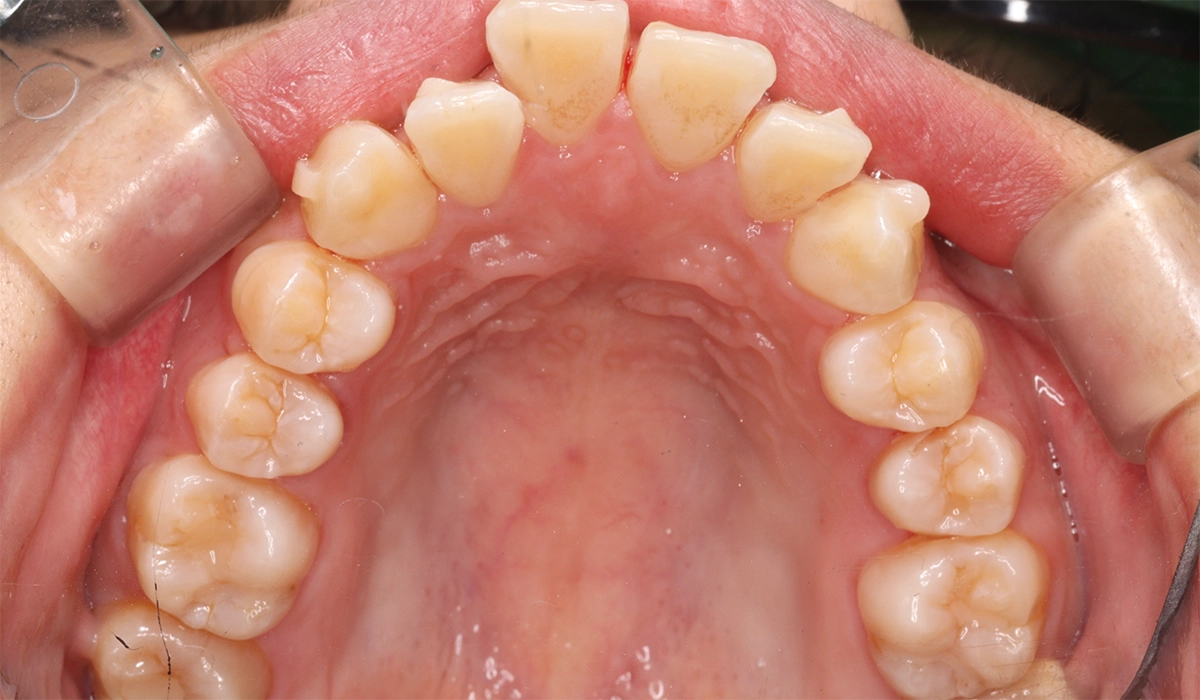

術前:上顎

術後:上顎